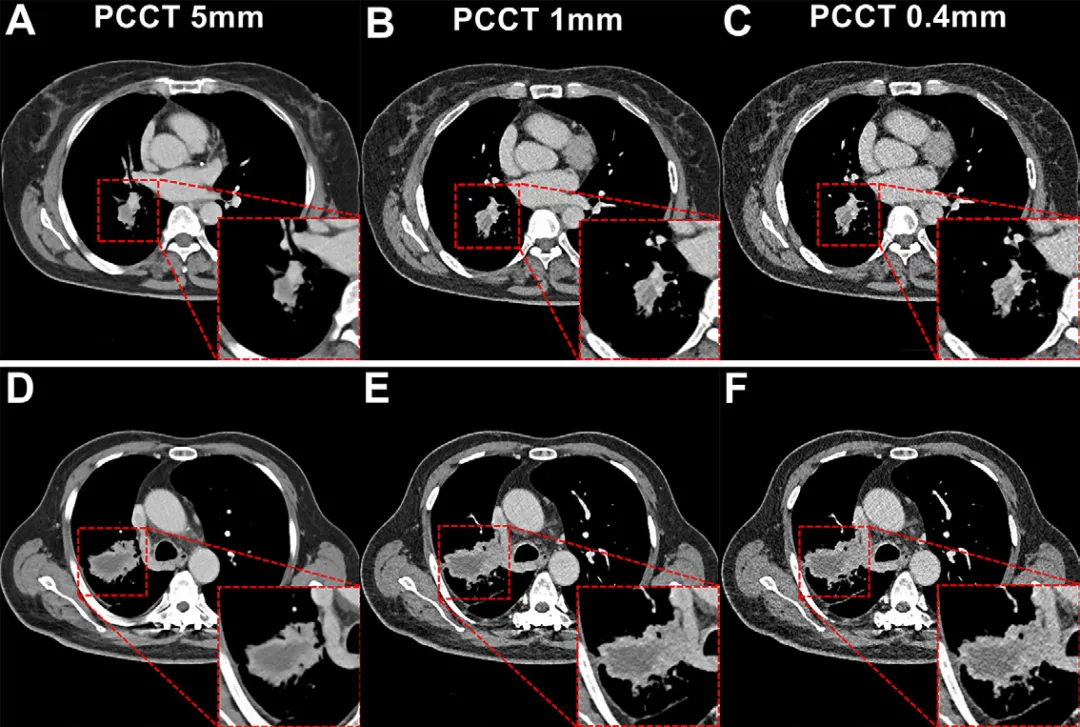

扫描与重建:PCCT使用双源量子CT(NAEOTOM Alpha),采用120 kV、UHR模式(准直120×0.2 mm),重建层厚包括5 mm、1 mm、0.4 mm。EID-CT采用相同造影剂浓度(350 mg I/mL),重建层厚为5 mm与1 mm。

图像质量提升:1️⃣PCCT在5 mm与1 mm层厚下噪声更低、SNR与CNR更高;0.4 mm层厚在噪声方面与EID-CT 1 mm相当,但空间分辨率显著提升。2️⃣主观评分显示PCCT 0.4 mm在“增强病灶内结构”显示上优于EID-CT,尤其在正常体重与小肿瘤(≤3 cm)患者中整体图像质量最佳。

亚组表现差异:1️⃣BMI越低,PCCT图像质量优势越明显;超重患者中PCCT仍改善主观评分,但CNR受噪声影响有所下降。2️⃣小肿瘤(≤3 cm)在0.4 mm层厚下结构显示更清晰;大肿瘤(>3 cm)则在1 mm层厚下边界对比更佳,提示应根据肿瘤大小个性化选择重建层厚。

图6:基于肿瘤大小的PCCT图像亚组分析,展示不同层厚在小肿瘤与大肿瘤中坏死区边界的显示差异。